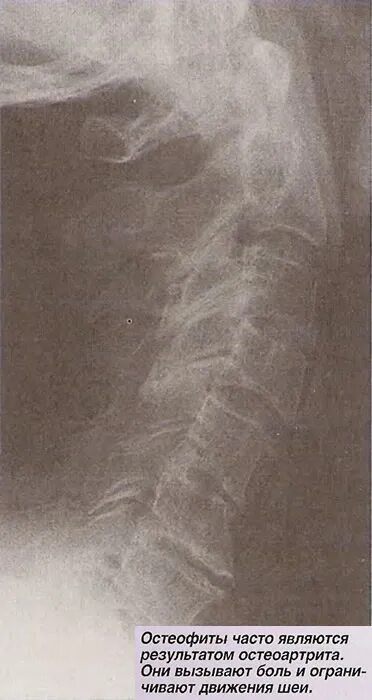

Остеофит причины